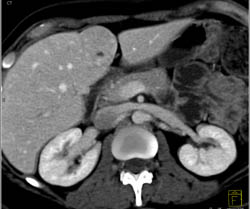

Focal Nodular Hyperplasia (FNH)